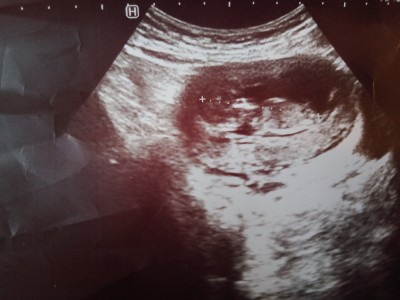

Cinsiyet tahmini sizce nedir anneler

Sizce cinsiyet tahmini yaparmısınız.

Gebelik haftası

12 haftalık